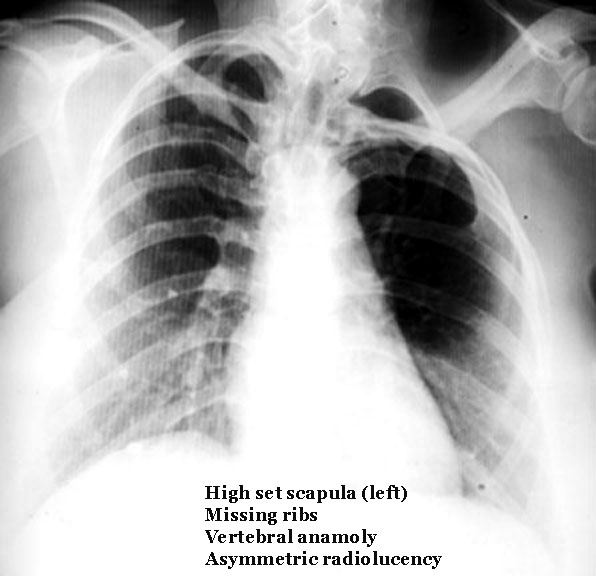

Genetic Services Policy Project Multiple Congenital Anomalies What are multiple congenital anomalies (MCA)? Infants with multiple congenital anomalies (MCA) are typically infants with: ... Fetch Doc